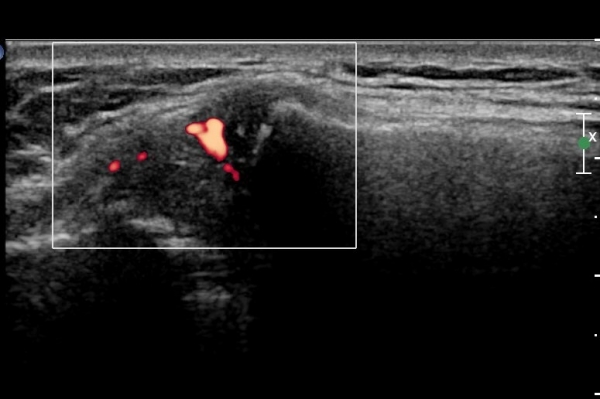

ÆÄ¿öµµÇ÷¯°Ë»ç¿¡¼­ °üÀýÀýºÎÀ§ Ç÷·ùÁõ°¡°¡ °üÂûµÊ(»çÁø 5).